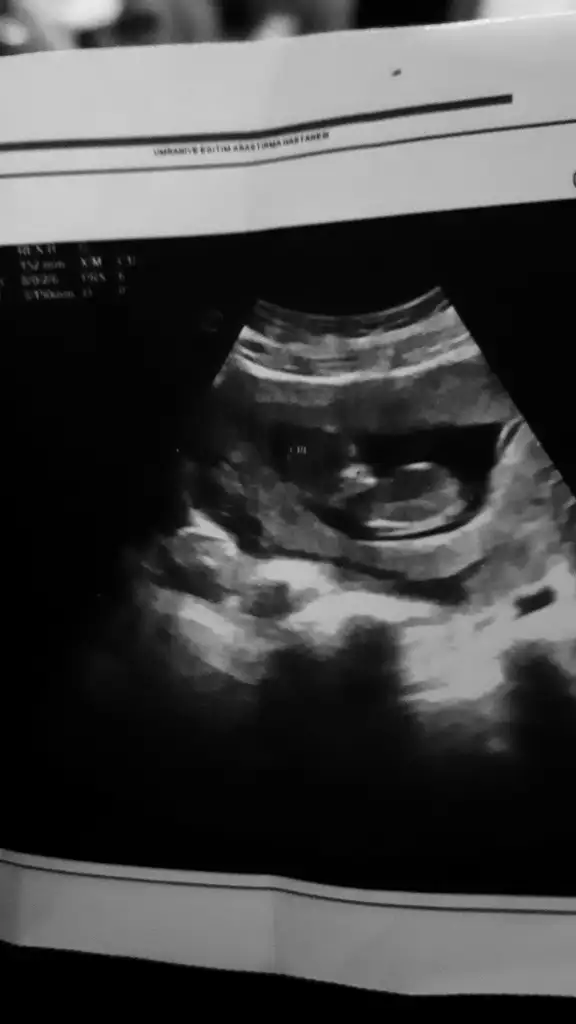

Merhaba 8+2 vajinal muayene sizce cinsiyeti nedir

Banada bakar misini 6+1 karından ultrasonKızlar 6-8 haftalık ultrason görüntülerinizi atın tahmin yapalım . Ya da cinsiyeti öğrenen annelerimiz 6-8 haftalık görüntülerini atsın bize de fikir olsun

Kıza benziyorKızlarr benimkinin cinsiyetini de tahmin edebilir misiniz biraz küçük ama merak iştekarından ultrason sat 6-6 doktora göre 6-3

Merhaba buda arkadaşımın 8 haftalık tahmin yapabilirmisinizErkek olduğunu düşünüyorum